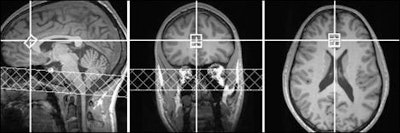

In the study, White and colleagues initially screened the mental and physical health of research subjects before performing MR spectroscopy to detect the concentration of neural compounds in key regions of the brain. The researchers specifically targeted the anterior cingulate cortex, which connects multiple brain networks involved in emotion, decision-making, and behavior.